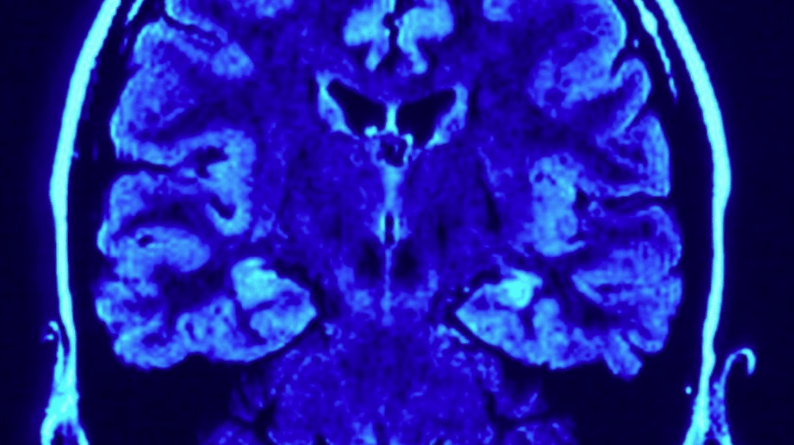

Naučnici su identifikovali pet glavnih “epoha” razvoja ljudskog mozga, u jednoj od najobuhvatnijih studija do sada o tome kako se neuronske veze mijenjaju od ranog djetinjstva do duboke starosti.

Studija, zasnovana na snimcima mozga skoro 4.000 ljudi – od beba mlađih od godinu dana do osoba od 90 godina – mapirala je neuronske veze i njihov razvoj tokom života. Istraživači su otkrili pet širokih faza, podijeljenih u četiri ključne “prelomne tačke” u kojima raspored mozga prelazi na drugačiju putanju – oko devete, 32., 66. i 83. godine života.